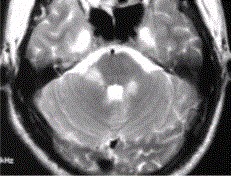

问题 患者男,35岁,肢体无力半年。头部MRI显示如下图。 关于MS与ADEM的区别,正确的是

选项 A.ADEM不累及灰质 B.两者均对称分布 C.ADEM复发常见 D.是否有病毒感染病史 E.两者均可能与病毒或自身免疫介导有关

答案 E